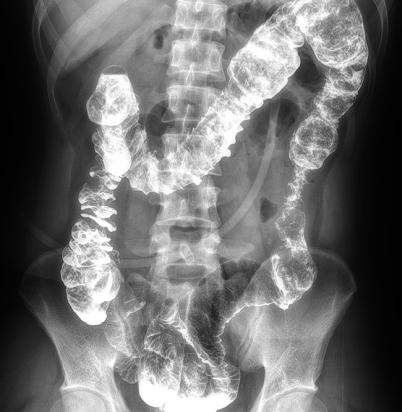

多功能動態(tài)平板DR,采用U型臂結構,具有靜態(tài)DR攝影、數(shù)字透視、數(shù)字造影和可視化攝影的功能。

電動旋轉內(nèi)平衡結構,可實現(xiàn)快捷擺位,滿足特殊體位的靜態(tài)與動態(tài)檢查。